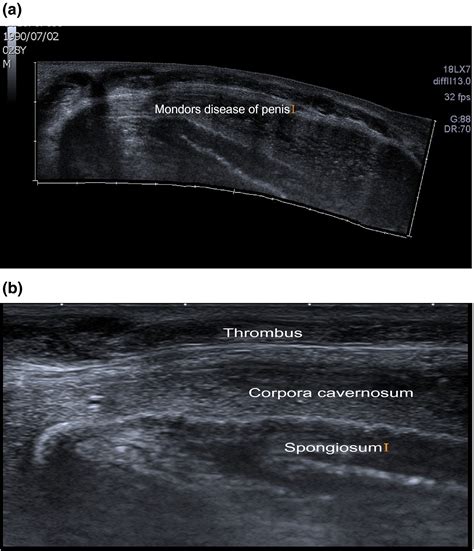

Ultrasound To visualize the affected vein and assess the presence of a blood clot.

It is important to note that Penile Mondor's disease can be mistaken for other conditions, such as Peyronie's disease or penile fracture. Therefore, a thorough evaluation by a healthcare provider is essential for an accurate diagnosis.